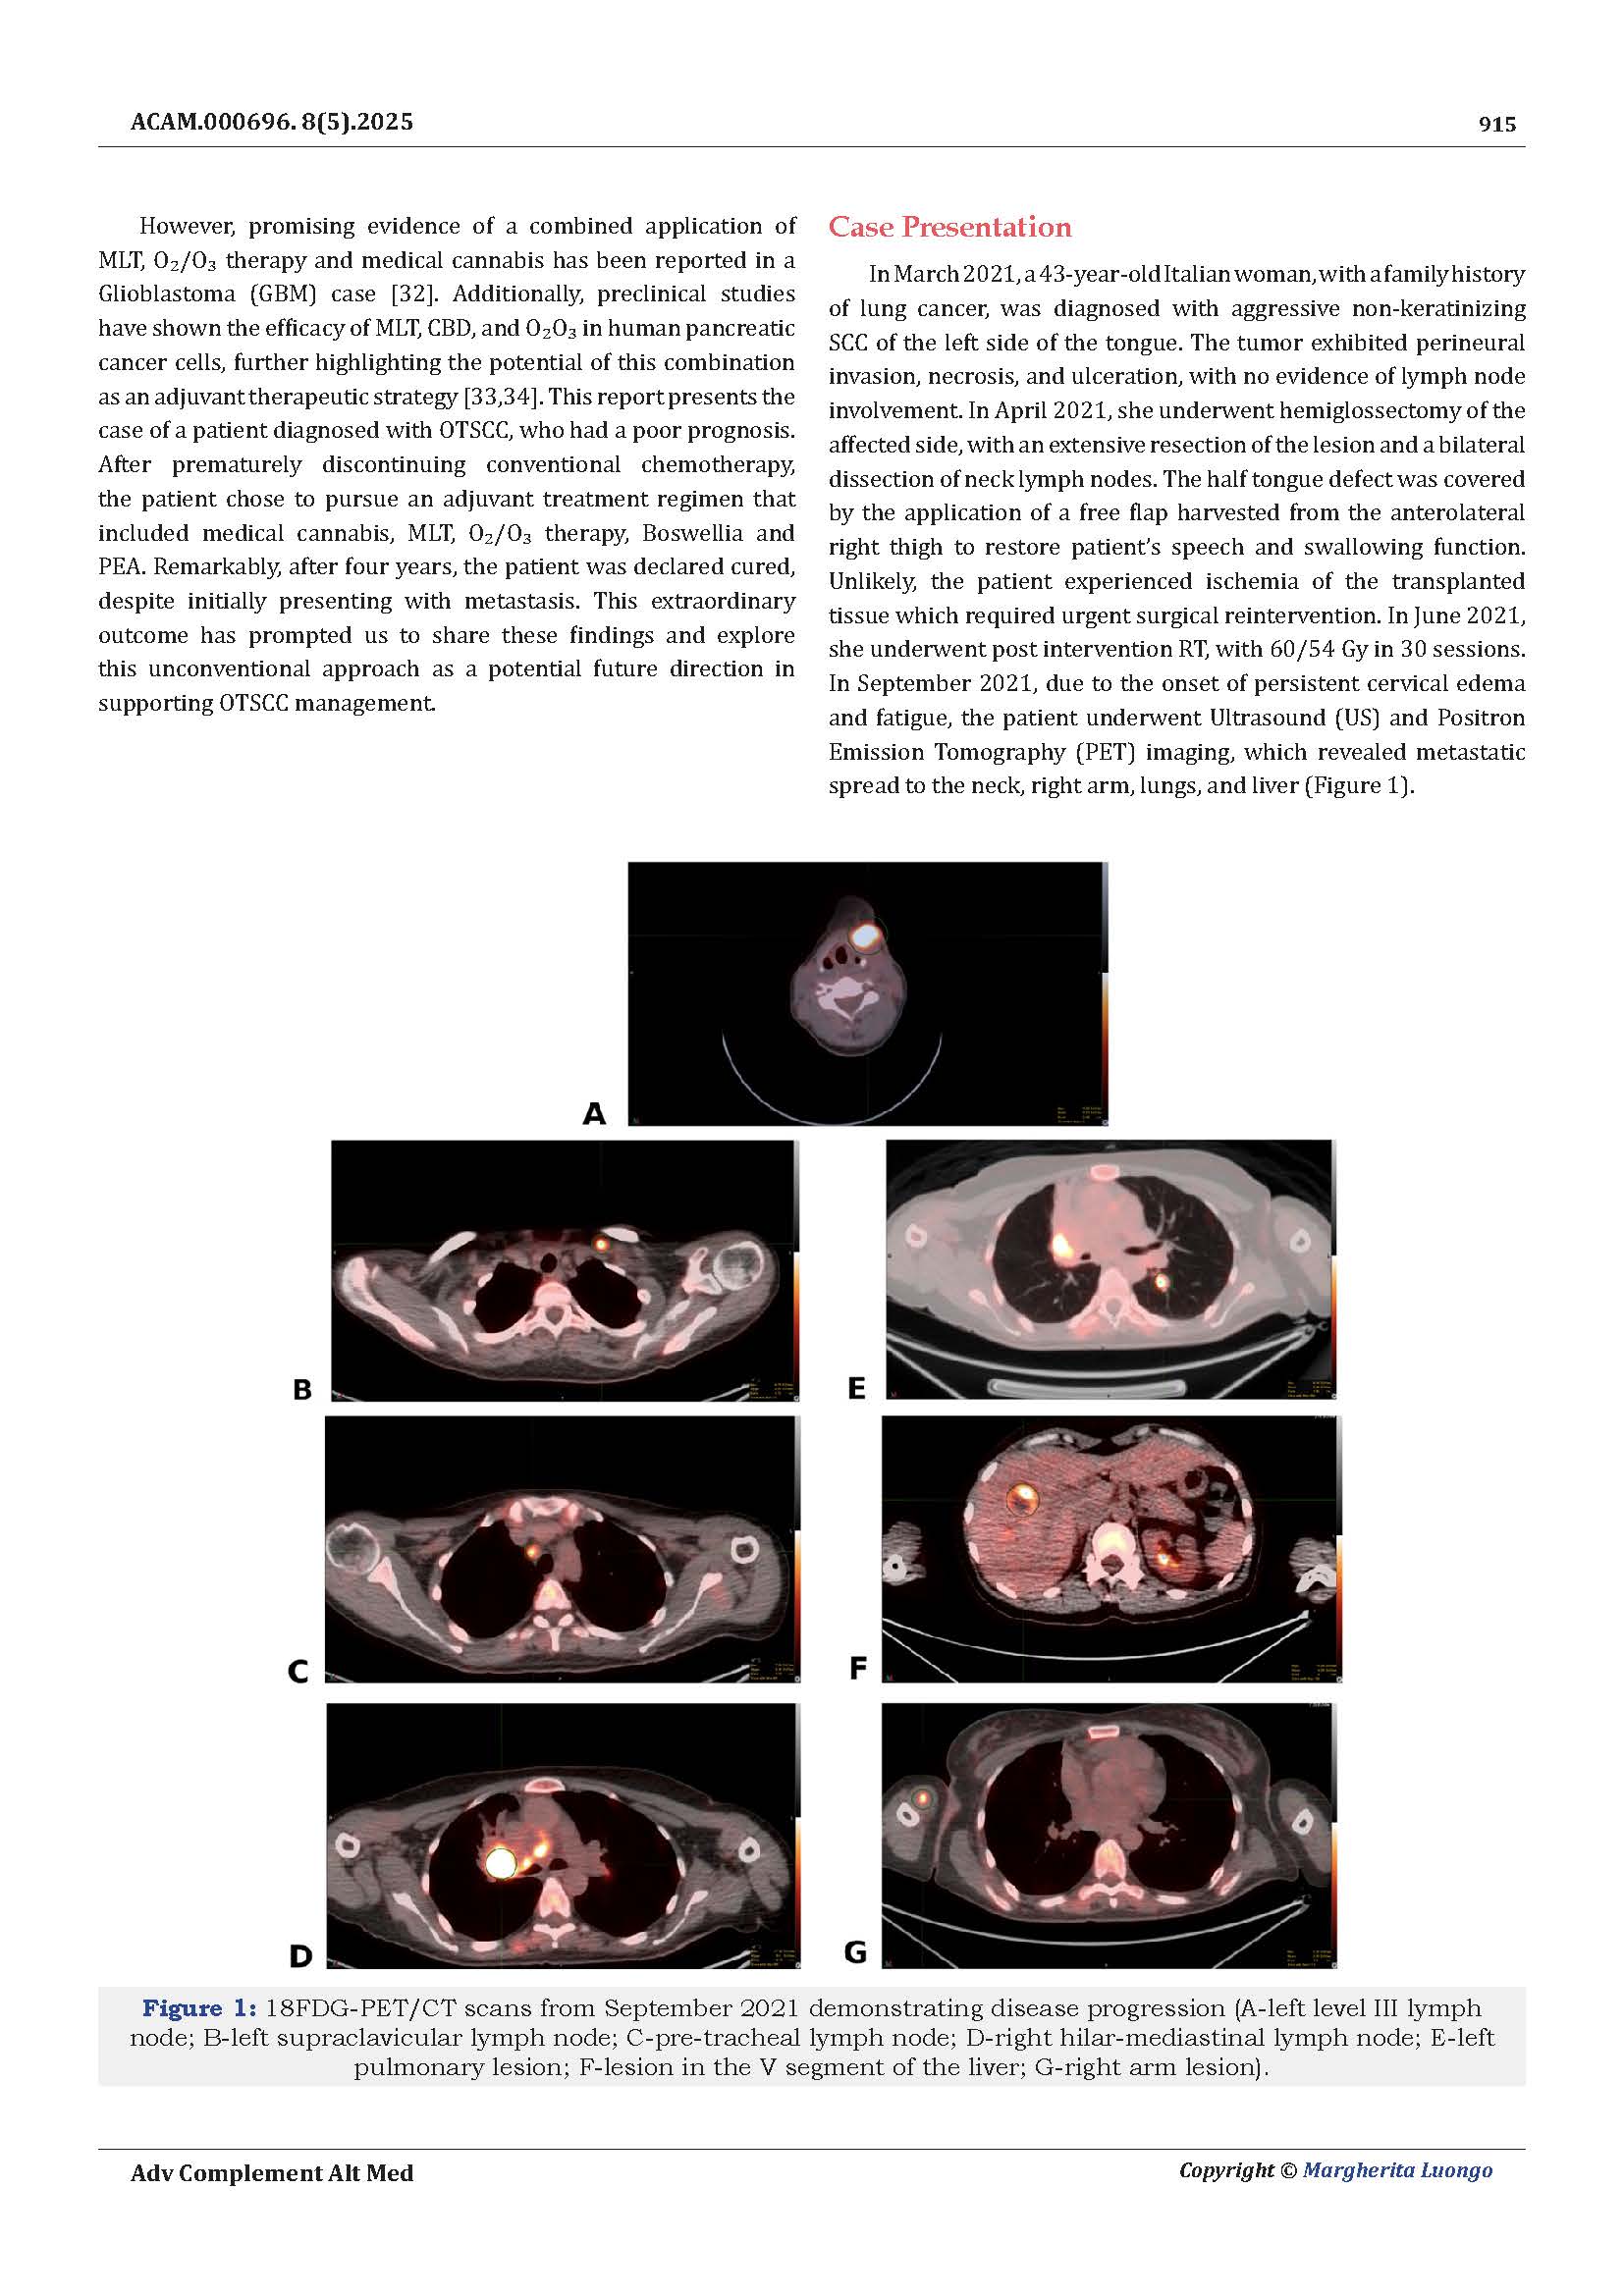

Dopo sei anni di monitoraggi costanti, le risonanze magnetiche hanno mostrato la stabilità della massa tumorale, senza progressione della malattia.